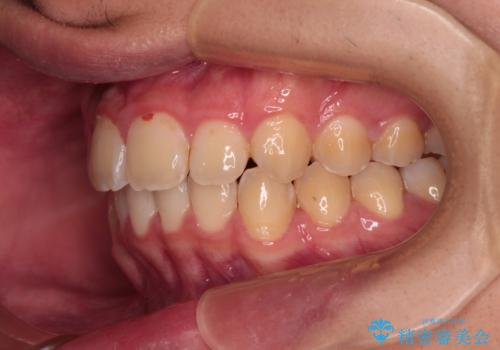

- 深く咬みこんだ前歯と、それに伴い前方に突出した上顎前歯を気にして来院された患者様です。

下顎の歯列は、奥歯が前方に傾斜し、前歯が上顎の歯の付け根に食い込むように内側に傾斜していました。

また、左右の犬歯の位置関係は上顎歯列が前方に位置する咬み合わせとなっており、インビザライン単体で治療するよりは、ワイヤー装置や補助装置を併用した方がより良い仕上がりになることが期待されました。

来院時は学生であったので、補助装置により上顎臼歯を後方に移動させ、下顎歯列はワイヤー装置による傾斜を改善させ、就職のタイミングでインビザラインにて仕上げていくこととしました。

インビザラインで難儀する部分をワイヤー装置にて確実に改善しておくことで、インビザラインのみで行うよりも治療期間を短縮するとともに、より理想的な歯列に近づけて仕上げることができました。